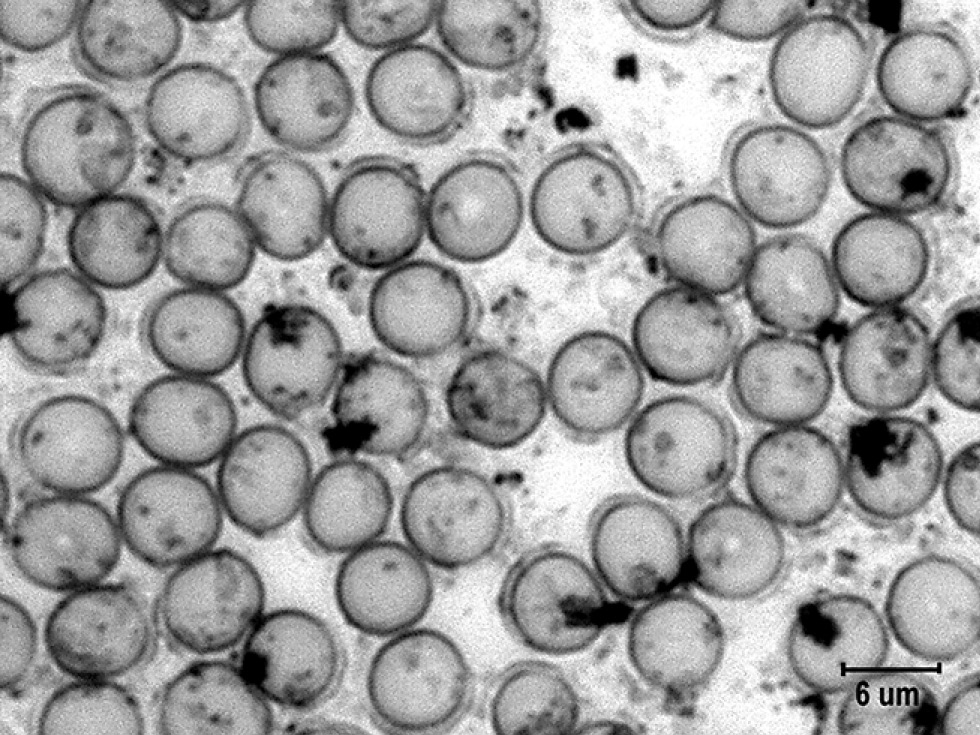

Согласно данным табл. 2 и рис. 3, у крыс, перенёсших острый стресс, число гранул малых размеров увеличилось в 3 раза (р <0,01), средних — в 1,3 раза по сравнению с контролем, но число гранул крупных размеров почти не изменилось. Общее число гранул катехоламинов в условиях стресса достигло 263±36,7 шт., что было почти вдвое больше, чем при спокойном бодрствовании (р <0,05). Ориентируясь на эти значения, можно предполагать почти двукратный прирост концентрации катехоламинов в крови при стрессе. Резкое повышение количества мелких гранул катехоламинов, вероятно, свидетельствовало об увеличении числа мест их связывания на мембране эритроцитов.

Рис. 3. Гранулы катехоламинов на поверхности эритроцитов в мазках крови крыс в условии острого стресса. Импрегнация азотнокислым серебром с докраской эозином. Ув. ×4000. / Fig. 3. Granules of catecholamines on the surface of erythrocytes in the blood smears of rats under acute stress. Impregnation with silver nitrate and final staining with eosin. Magnification, ×4000.

Рост числа гранул катехоламинов на эритроцитах в условиях острого стресса также говорит в пользу адренергической природы гранул и согласуется с представлениями о повышении уровня катехоламинов в крови при стрессе и ростом частоты сердечных сокращений (ЧСС) в условиях той же модели стресса [14].